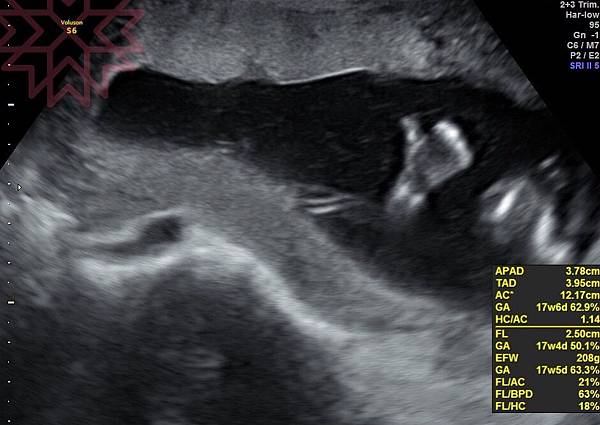

做羊穿最好的時機是16周18周,最好滿16周,進入第17週的時候再來做,

因為這時候是羊水量足夠,胎兒又不至於過大的時期,檢驗做起來相對安全,

如果周數太少,醫生檢查覺得羊水量不夠,是有可能當天被退貨的而我選擇17W+1這一天。

這階段也是柯P親自來操作,會檢查小孩的四肢發展、基本構造、羊水量...等等